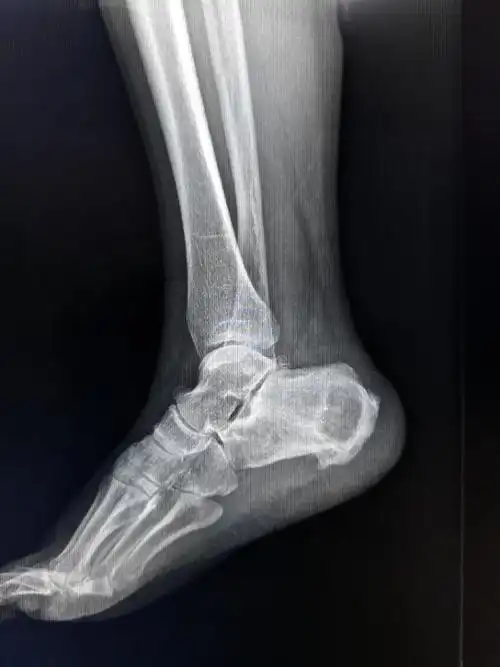

足侧位x线解剖图_有来医生

踝关节正位x线超声:可代替或结合mri检查软组织的损伤;ct:能进一步

我们来学习巩固解剖下及x线影像下的跟骨是什么样的

详细的踝关节x线解剖变异解读测量